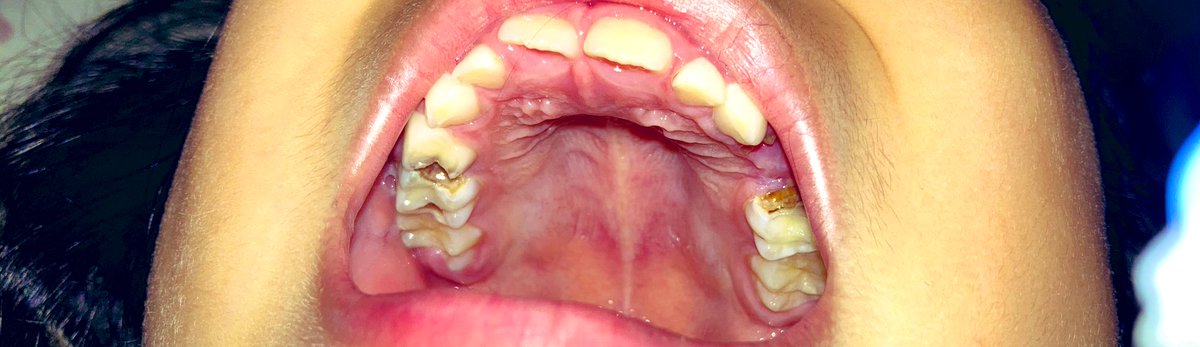

むし歯は、虫がつくるのではありません。 歯垢 ( しこう ) の中のバイキン(ミュータンス 菌 ( きん ) )がつくりだす 酸 ( さん ) によって、歯がとけていく 病気 ( びょうき ) です。 ミュータンス菌は、 砂糖 ( さとう ) の入ったあまいものを 食 ( た ) べると、 活発虫歯になりやすいのは、唾液の出口から遠い上の前歯や上下の奥歯。 ただし、上の前歯は痛みを感じやすいので、奥歯から磨き始めましょう。 ポイントは ・歯ブラシは歯に直角にあてる ・力を入れすぎない (100~150gが目安。 キッチンスケールを利用ひどい虫歯の治療例(47歳女性) 治療前 上の歯全体がすべてがひどい虫歯で、いらした方です。 一見すると、もうどうしてよいかわからないような状態ですが、診査の結果、歯の根はわりあいしっかりしていましたので、クラウンレングスニングなどの

虫歯 画像 子供-虫歯の写真、画像で見る進行度 進行度によって処置方法が様々です。 当院では1回目で見た目が改善。 歯科治療恐怖症でも静脈内鎮静法で処置できます。 忙しくて通院できない方にもおすすめです。 進行度C0、C1、C2、C3、C4を写真で見てみましょう。医薬部外品モンダミンkid's ぶどう味 子供用マウスウォッシュ 250mlがマウスウォッシュストアでいつでもお買い得。当日お急ぎ便対象商品は、当日お届け可能です。アマゾン配送商品は、通常配送無料(一部除く)。

いまは、むし歯ができるしくみが気になっている。 妹のクリアちゃんは、歯みがきが大すき。 ごはんを食べたら、歯をみがくのが 習慣 ( しゅうかん ) になっていて、むし歯が1本もないのがじまん!虫歯治療法・予防法・子供(乳歯)のむし歯・画像(写真) 暮らし カテゴリーの変更を依頼 記事元 wwwhachannelcom 適切な情報に変更 虫歯の進行度はc0~c4の5段階子供のころから予防する習慣をつけて健康な歯を保ちましょう虫歯の進行度は「c0(シーオー)~c4(シーフォー)」という5段階で表します。c0 とは 「c3虫歯」の症例画像を中心に紹介します。

虫歯予防の最終目標は、15歳で永久歯の虫歯が1本もないこと です。 そうすれば、その後に新しく虫歯ができることはあまりなくなります。 おとなになってから必要になる虫歯治療のほとんどは、それ以前にすでに虫歯になりかかっていた歯、もしくは子どものころに治した虫歯の再治療です。子供の乳歯と虫歯に関する情報です。 子供の歯について興味のある方は是非ご活用ください 子供 乳歯 虫歯 治療 排膿 受口 画像 歯茎 前歯 抜歯 東京 大阪 名医 GVBDO子供の乳歯の虫歯は歯の白変、黒変、穴などの変化を見逃すな! 乳歯 虫歯が与える悪影響・子供の歯を守るオーラルケア 乳歯の虫歯とは一体どんな感じ?初期発見が重要です!画像 虫歯の写真、画像で見る進行度 ザ・ホワイトデンタルクリニック